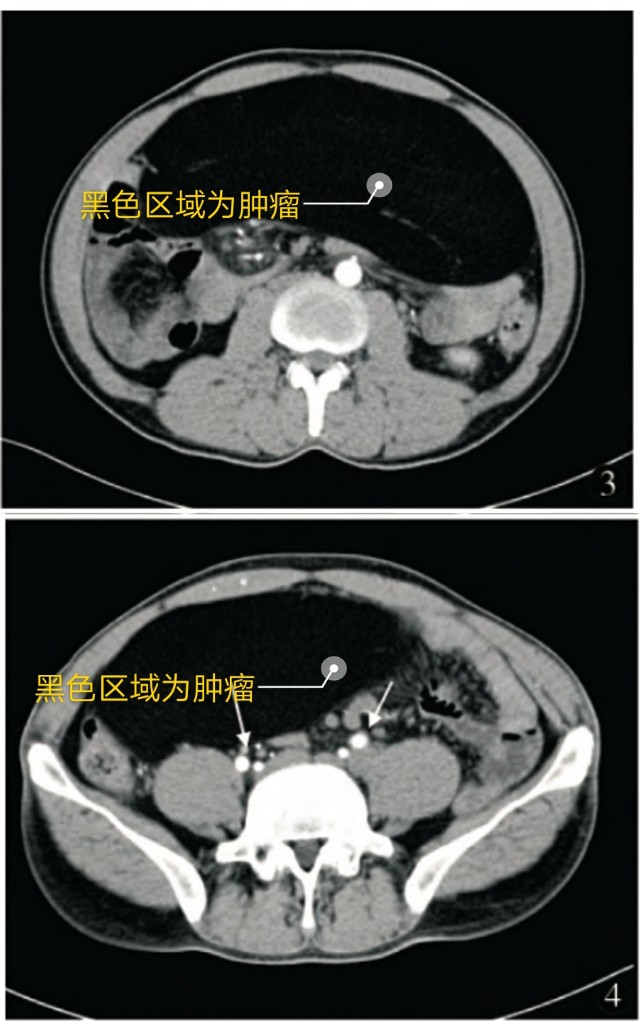

入院后完善CT检查

腹腔盆腔可见巨大肿块,占满腹盆腔,病灶呈脂质低密度,其密度不均,增强后无明显强化,肝脏受压,肝门部变形,胰腺受压变形。肿瘤体积约32×22×15cm。考虑为脂肪肉瘤。

肿瘤上腹部开始出现,压迫胃

肿瘤延续至中腹部,压迫胰腺组织、肠管